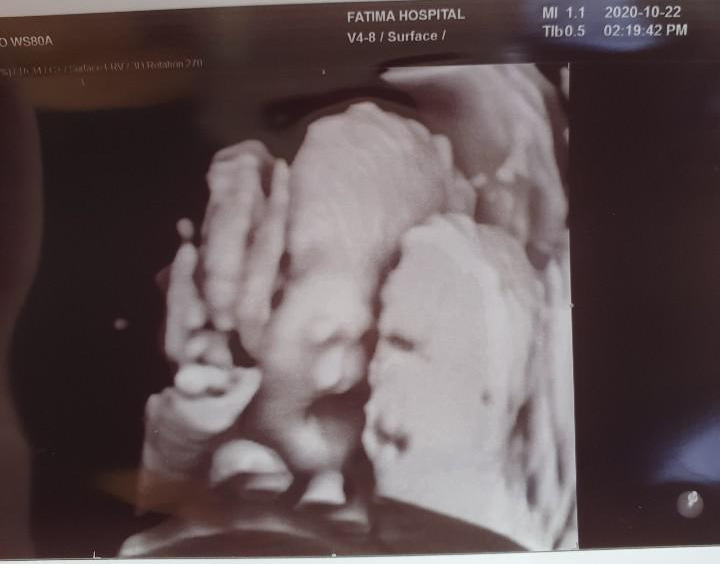

그러던 중 아내의 30주 초음파 검사를 함께 가게 되었는데요. 그때 마주한 찰떡이의 모습에 저의 마음이 더욱 단단해지는 것을 느꼈어요

찰떡아 안녕, 하품은 왜 하는거니?